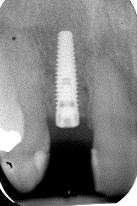

Single Tooth Implant: Potential Pitfalls

FIGURE 22--Implant radiograph.

The single tooth implant is often promoted by dental implant companies as being “easy”, yet this is often far from the truth. The single tooth replacement often involves adjacent teeth, anterior aesthetics, lost teeth with “history” and limited interocclusal space/ access. The novice or cavalier dentist may feel confident undertaking this responsibility following a couple … Read more